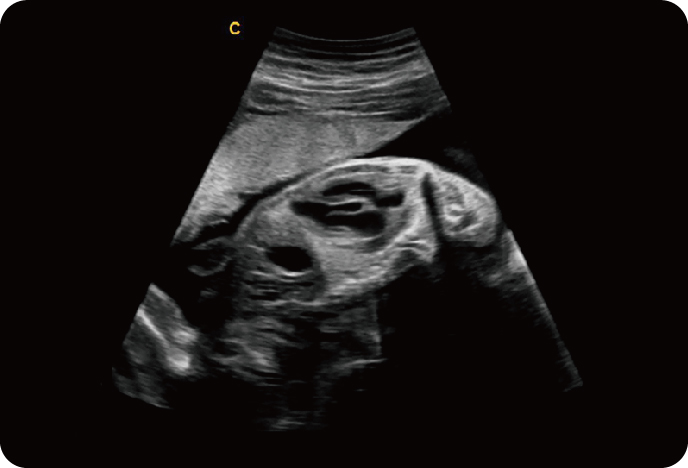

4D Объемный